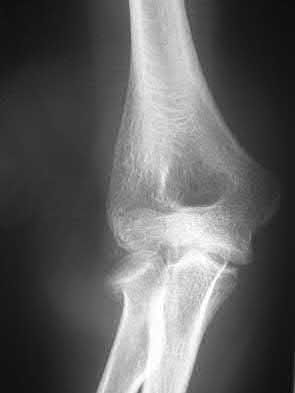

Fragment excision and triceps reattachment is ideally indicated for which of the following situations?

- A 30-year-old woman with a closed comminuted fracture involving more than 50% of the joint surface

- A 30-year-old woman with an open transverse olecranon fracture that is proximal to the trochlear notch

- A 55-year-old woman with an oblique olecranon fracture through the coronoid process

- A 75-year-old woman with an oblique fracture through the coronoid process

-

An 85-year-old man with a comminuted fracture involving less than 50% of the proximal joint surface

Corrent answer: 5

Fragment excision and reattachment of the triceps tendon may be indicated in a select group of elderly patients with osteoporotic bone in whom the olecranon fracture fragments involve less than 50% of the joint surface, and are too small or too comminuted for successful internal fixation. The triceps tendon is reattached with nonabsorbable sutures that are passed through the drill holes in the proximal ulna. In a physiologically young patient, internal fixation should be performed. Plate fixation would be appropriate for comminuted fractures, whereas tension band wiring could be used for a simple transverse fracture. Oblique fractures passing through the coronoid process are best treated by plate fixation.